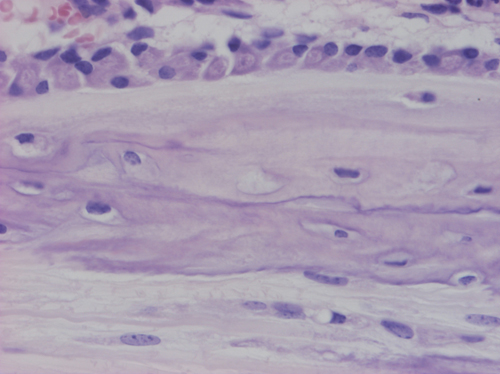

Los osteoblastos (flecha) son las responsables de la síntesis de la matriz orgánica, el osteoide, y median su mineralización. Se disponen alineados en una capa sobre las superficies óseas.

Los osteocitos (punta de flecha) son osteoblastos inactivos atrapados en el hueso formado. Se trata de células maduras localizadas en el seno de la matriz ósea en el interior de espacios llamados lagunas. Son células ovoides a aplanadas, con grandes prolongaciones que se introducen en los conductos calcóforos. Se encargan del mantenimiento de la matriz ósea.